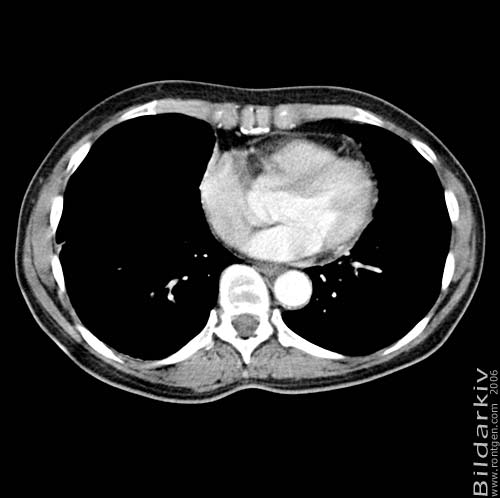

Snitt över thorax med kontrast. Sk. mediastinum-fönstersättning.

Mediastinum